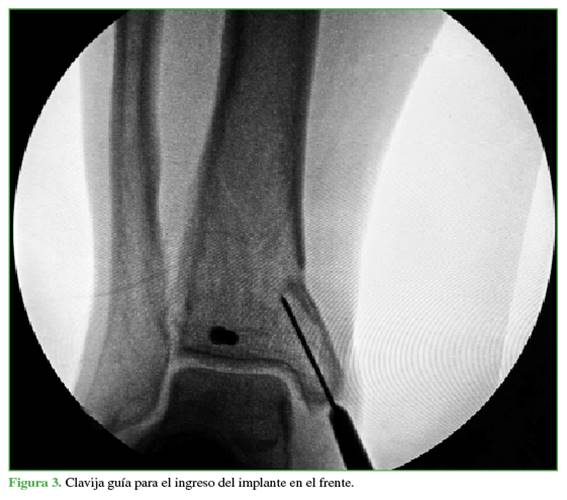

A continuación, se crea un abordaje de 3 cm desde la punta de maléolo tibial hacia distal (Figura 2). Mediante una clavija se ubica el sitio de ingreso en el centro del maléolo tibial, en ambos planos (Figuras 3 y 4), para luego agrandar con una fresa canulada la zona de ingreso (Figura 5), después se coloca una guía olivada (Figura 6) y, a través de un protector de partes blandas, se fresa el canal medular (Figura 7).